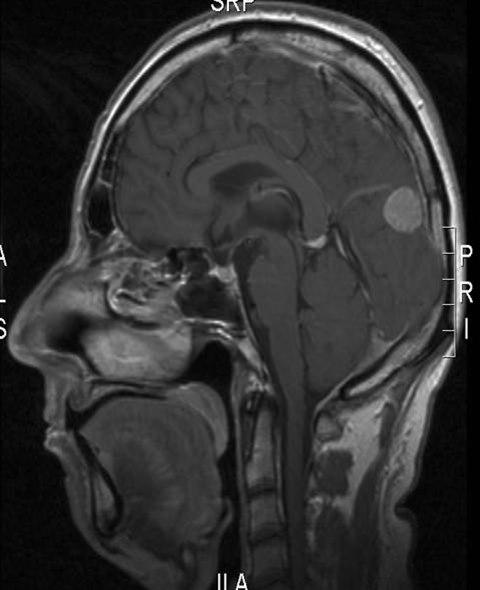

Meningeom, sagittalt snitt

Gjengitt med tillatelse av Radiologisk avdeling, Universitetssykehuset Nord-Norge